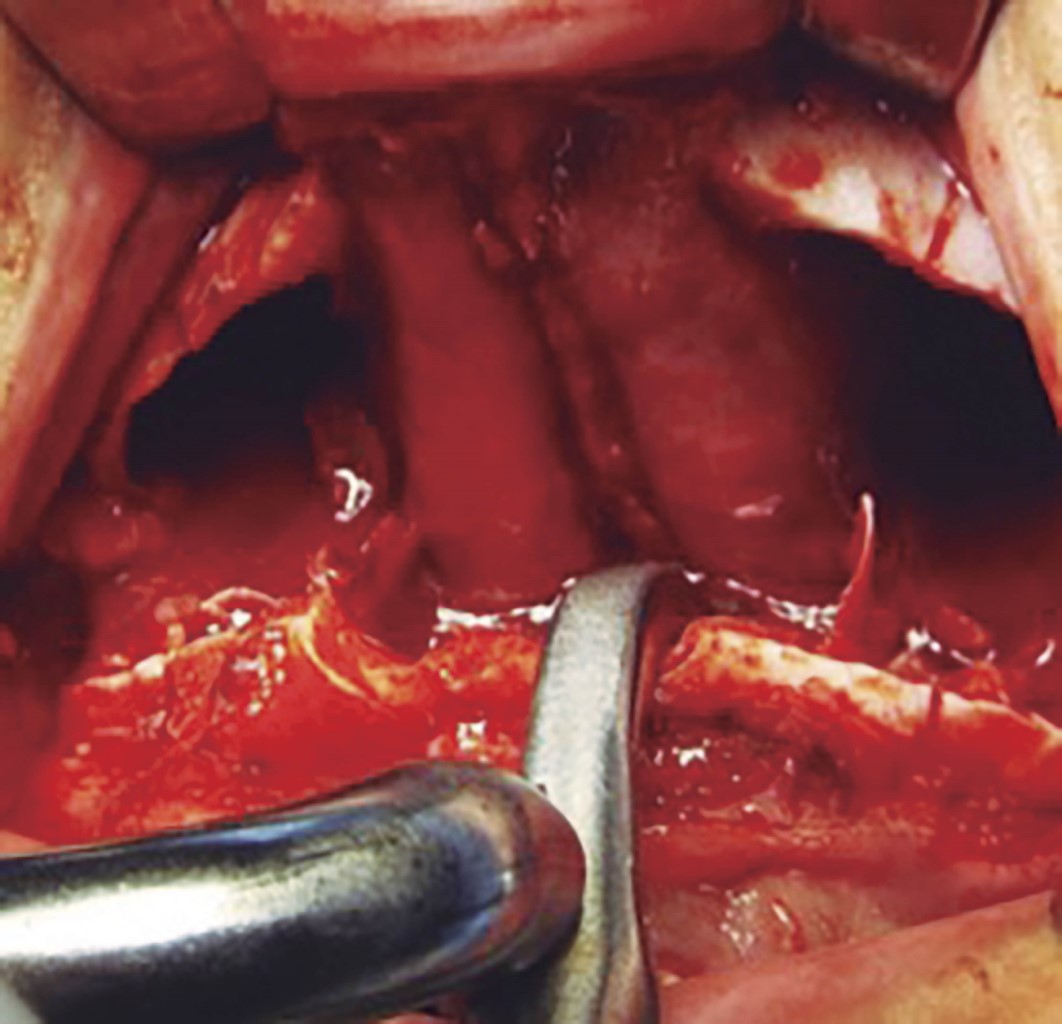

Se procede a la disección de la mucosa nasal. En el piso de la fosa nasal ha de disecarse hasta 30 mm a posterior (Figura 2) y enseguida se efectúa marcaje sobre el lecho óseo de acuerdo al tipo de osteotomía a realizar. Se colocan marcas de referencia (Figura 3). Se realiza osteotomía con sierra reciprocante, iniciando en la pared lateral de la apertura piriforme, protegiendo la mucosa nasal previamente con una legra, hasta la región pterigomaxilar. Una vez completado el corte se realiza la disyunción de las apófisis pterigoides laterales y mediales del seno maxilar mediante osteótomos y se procede a realizar el descenso maxilar introduciendo pinzas de Smith en la osteotomía del buttress maxilomalar (Figura 4), de manera gradual y verificando la integridad de la mucosa nasal. Se realiza este paso de manera bilateral. Se procede a introducir cincel de septum en la apertura piriforme (Figura 5). Se inserta la pinza de Smith en el buttress anterior y de igual forma se abre de manera gradual verificando también la integridad de tejidos blandos. Se completa la disyunción del maxilar y se moviliza en su totalidad: anterior, lateral e inferiormente (Figura 6). Se regularizan espículas, si las hay, y se reposiciona el maxilar de acuerdo a lo planeado para la cirugía. Se fija el maxilar con miniplacas de osteosíntesis en L en la región medial del buttress nasomaxilar y en el buttress cigomaticomaxilar ambos de manera bilateral, se verifica hemostasia y se colocan puntos de sutura en la mucosa maxilar. Se procede a seguir con la cirugía ortognática.2,6,14,15,19

Figura 4